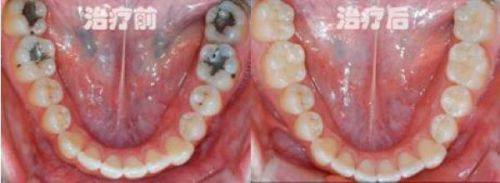

1. 口腔修复技术:采用精良的材料和工艺,能够精细修复牙齿缺损、缺失等问题,修复牙齿的美观和功能。